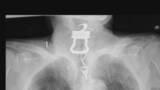

2022年、大阪市内の病院に入院していた男性(当時82)の喉から12センチの「カギ」が見つかりその後...